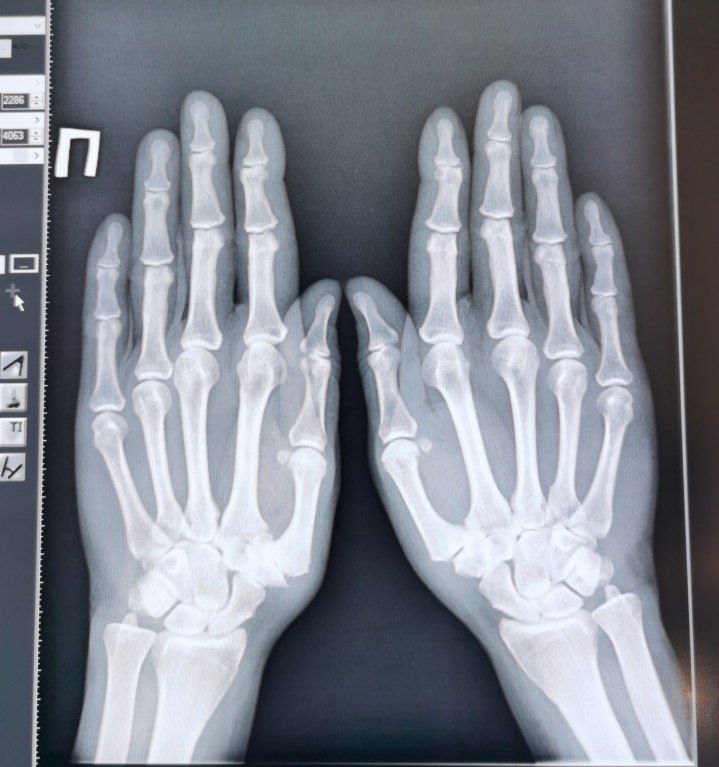

lizabes in Radiology/Рентгенология Чат

Коллеги, подскажите, кость-трапеции правого запястья- вариант нормы? Пальцы указательне как описать?

Анамнеза пока нет, думаю просто болит. Не травма точно. Доктор на операции карту ей ещё не заполнила